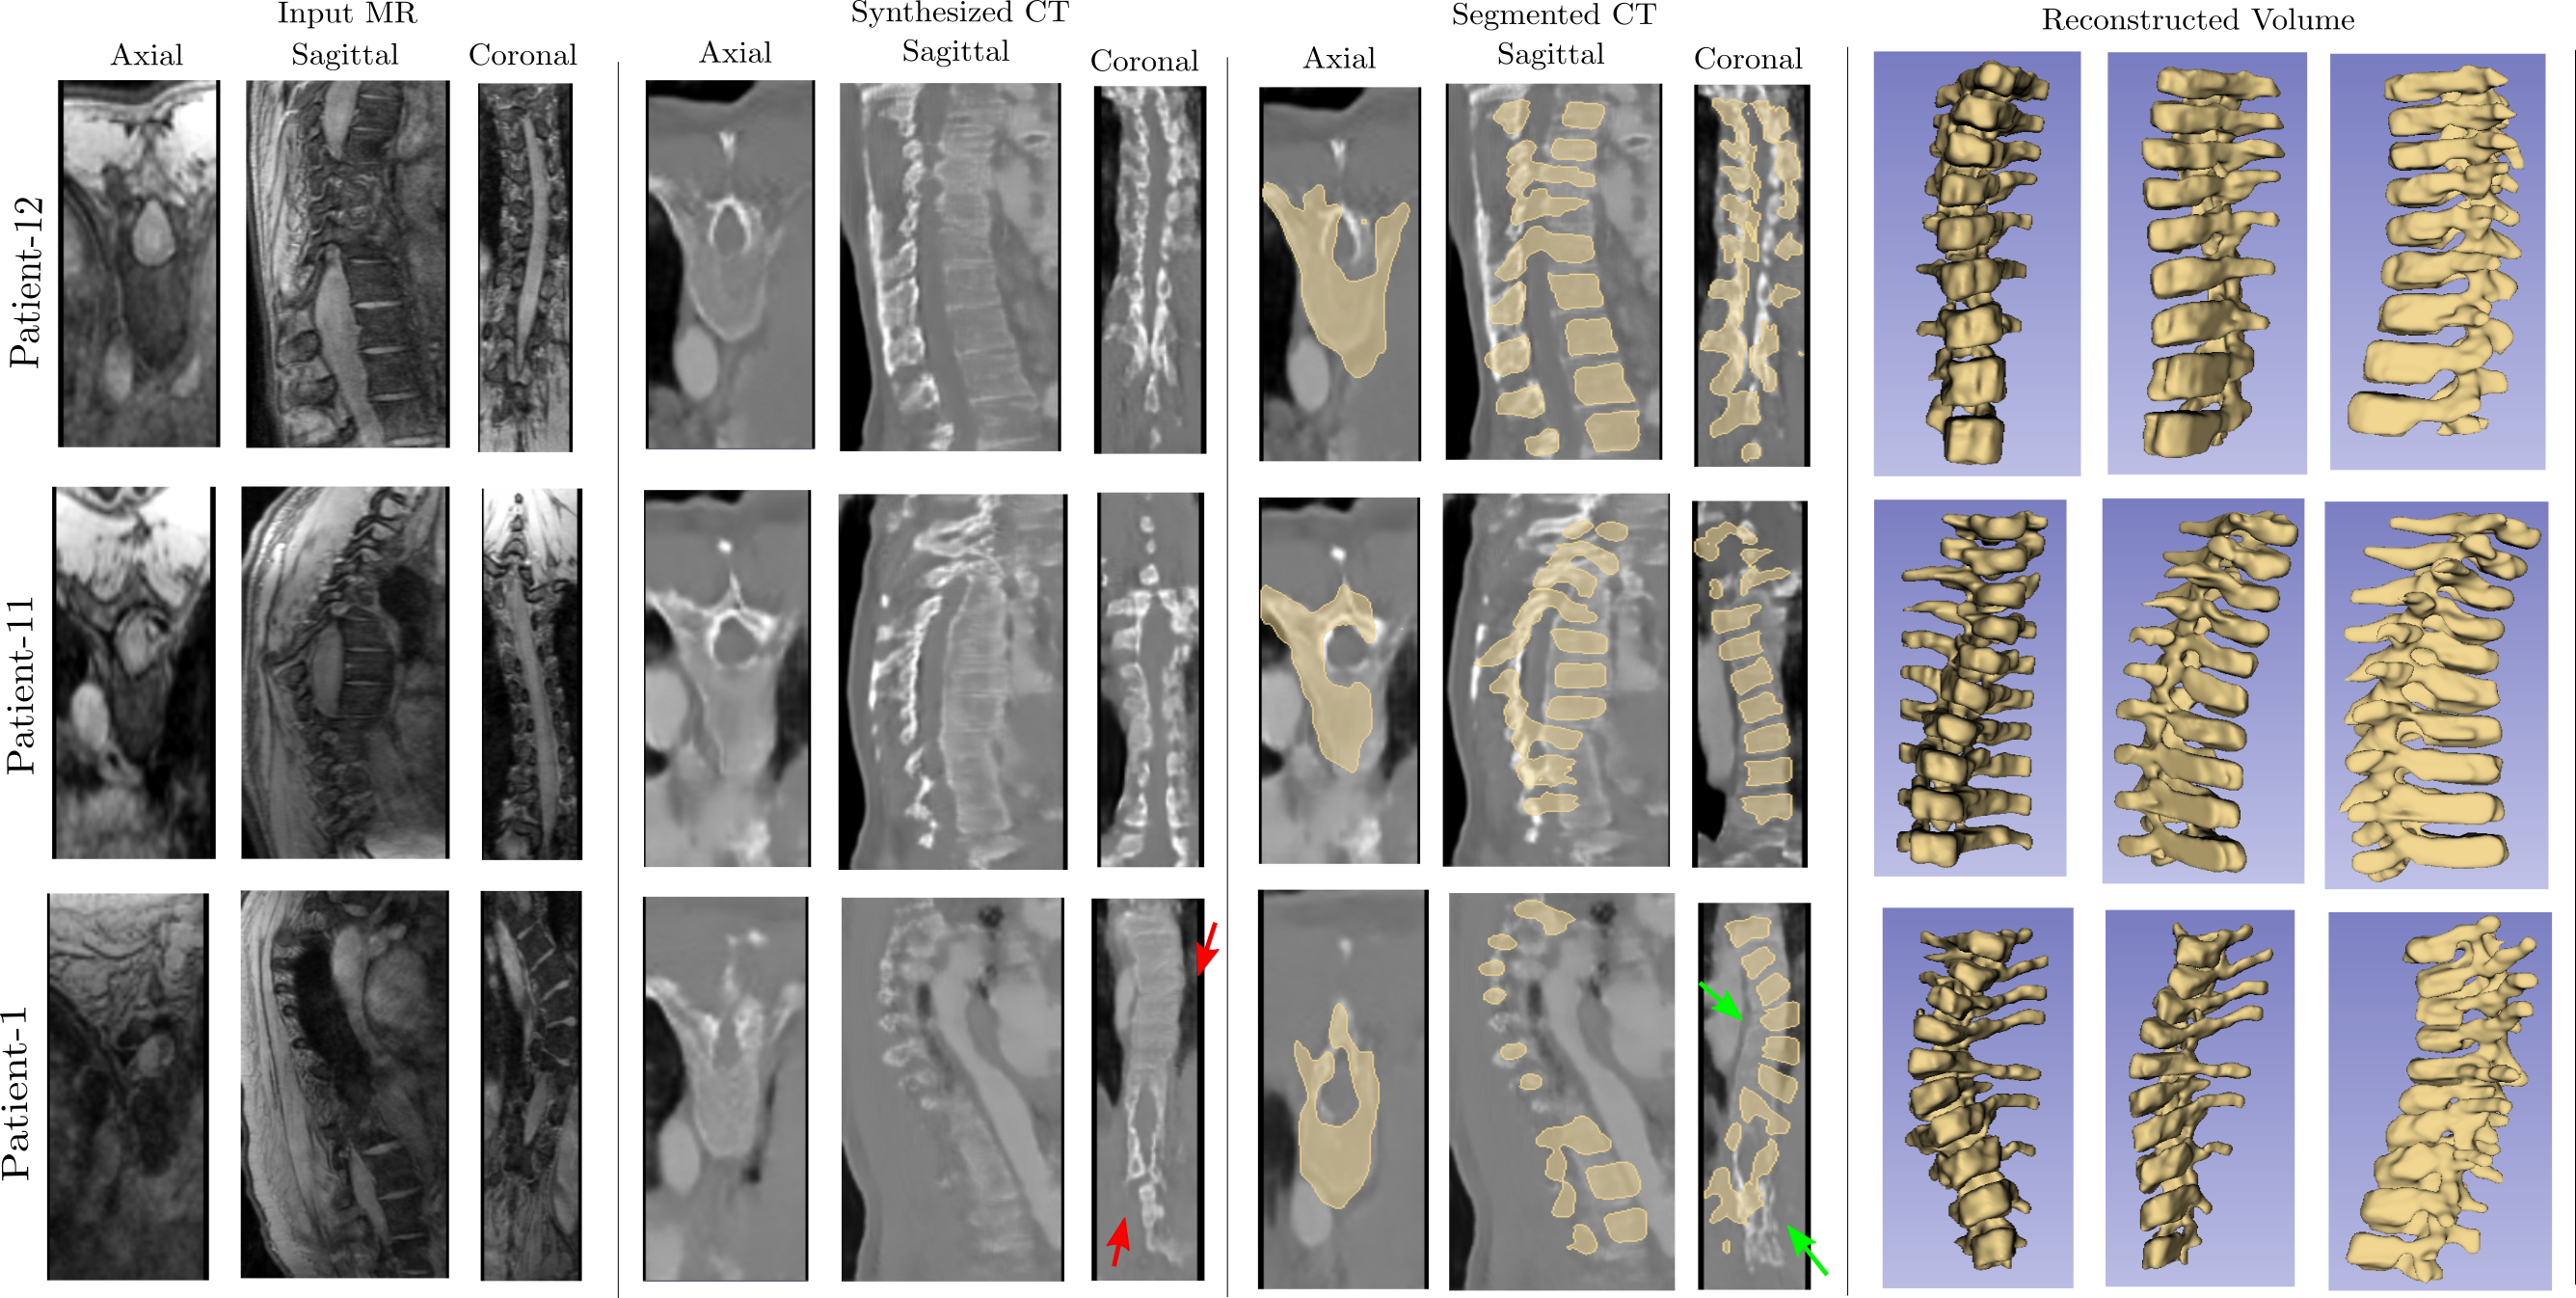

In this section, we present both qualitative and quantitative analysis of our model’s performance on a test data of 3 scoliotic patients (P1, P11 and P12). Figure 3 shows the qualitative results obtained at each stage. For the regions of the spine where the curvature is normal, we found that the model learned to identify the difference in the intensities between bones and the soft tissues in MR and CT volumes and is able to translate them (figure 3, Patient-12 and Patient-11). However, some incorrect translations in the synthesized CT volumes were also observed. This was prominent in P1’s case (figure 3, third row, red arrows) where the spinal curvature was too high for a good translation. As a result, the subsequent segmentation errors due to Otsu thresholding were manually corrected using Slicer’s paint-brush tool (figure 3, third row, green arrows). This is attributed to the unpaired nature of the input data and a relatively high anatomical variation in the scoliotic spine. Even though the segmentation is not completely automatic due to translation errors, post-processing of the segmentation resulting from synthesized CT volumes is certainly easier compared to a direct segmentation from MR volumes. Furthermore, we note that even in the case of real CT volumes, some manual intervention was necessary in order to remove the segmented structures other than the spine after thresholding.

Refer to caption

Figure 3: 3D segementation and volume reconstruction of the vertebral column. Top \to Bottom: Results corresponding to the scoliotic spines of Patients 12, 11, and 1 respectively. Right \to Left: First column shows 2D slices of MR volumes, Second column shows the synthesized CT volumes, Third column shows the result of 3D segmentation by Otsu thresholding + post-processing, Fourth column shows the reconstructed 3D models of scoliotic spines. The red arrows show the translation errors and the green arrows show the corrected segmentations.